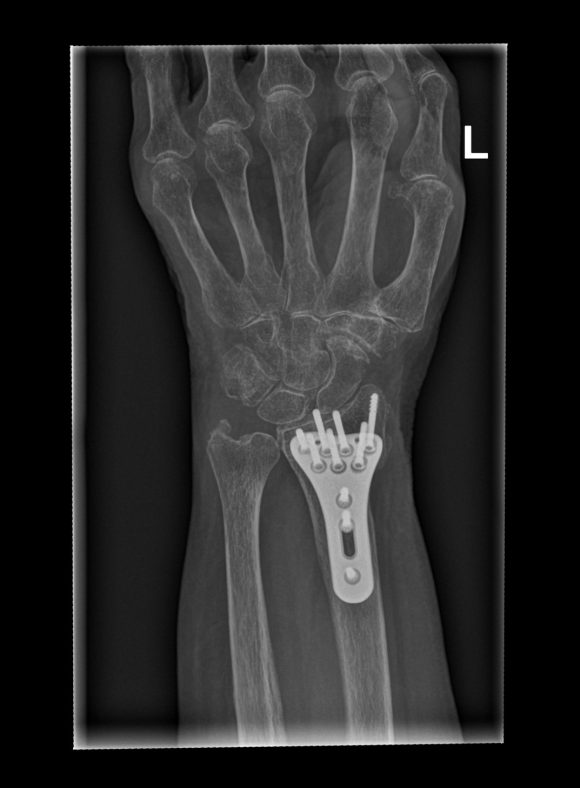

De behandeling van een polsfractuur hangt af van de aard en ernst van de breuk. Bij niet-verplaatste breuken kan conservatieve behandeling nodig zijn, waaronder gipsimmobilisatie gedurende een 6-tal weken, rust en pijnstillers. Indien er wel een operatie nodig is, wordt de breuk goed gezet en met een plaat en schroeven gefixeerd. Na 2 weken mag de patiënt dan meestal reeds bewegen met de pols zonder kracht te zetten